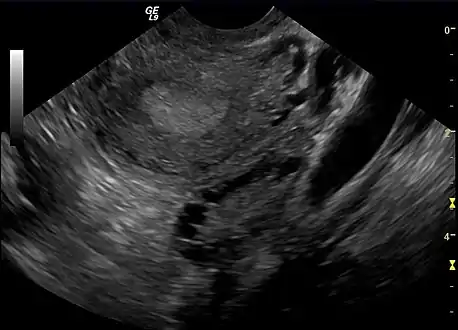

A polycystic ovary

The syndrome acquired its most widely used name due to the common sign on ultrasound examination of multiple (poly) ovarian cysts. These "cysts" are in fact immature ovarian follicles. The follicles have developed from primordial follicles, but this development has stopped ("arrested") at an early stage, due to the disturbed ovarian function. The follicles may be oriented along the ovarian periphery, appearing as a 'string of pearls' on ultrasound examination.[86]

• Gynecologic ultrasonography, specifically looking for small ovarian follicles. These are believed to be the result of disturbed ovarian function with failed ovulation, reflected by the infrequent or absent menstruation that is typical of the condition. In a normal menstrual cycle, one egg is released from a dominant follicle – in essence, a cyst that bursts to release the egg. After ovulation, the follicle remnant is transformed into a progesterone-producing corpus luteum, which shrinks and disappears after approximately 12–14 days. In PCOS, there is a so-called "follicular arrest"; i.e., several follicles develop to a size of 5–7 mm, but not further. No single follicle reaches the preovulatory size (16 mm or more). According to the Rotterdam criteria, which are widely used for diagnosis of PCOS,[10] 12 or more small follicles should be seen in a suspect ovary on ultrasound examination.[21] More recent research suggests that there should be at least 25 follicles in an ovary to designate it as having polycystic ovarian morphology (PCOM) in women aged 18–35 years.[95] The follicles may be oriented in the periphery, giving the appearance of a 'string of pearls'.[96] If a high-resolution transvaginal ultrasonography machine is not available, an ovarian volume of at least 10 ml is regarded as an acceptable definition of having polycystic ovarian morphology. rather than follicle count.[95]